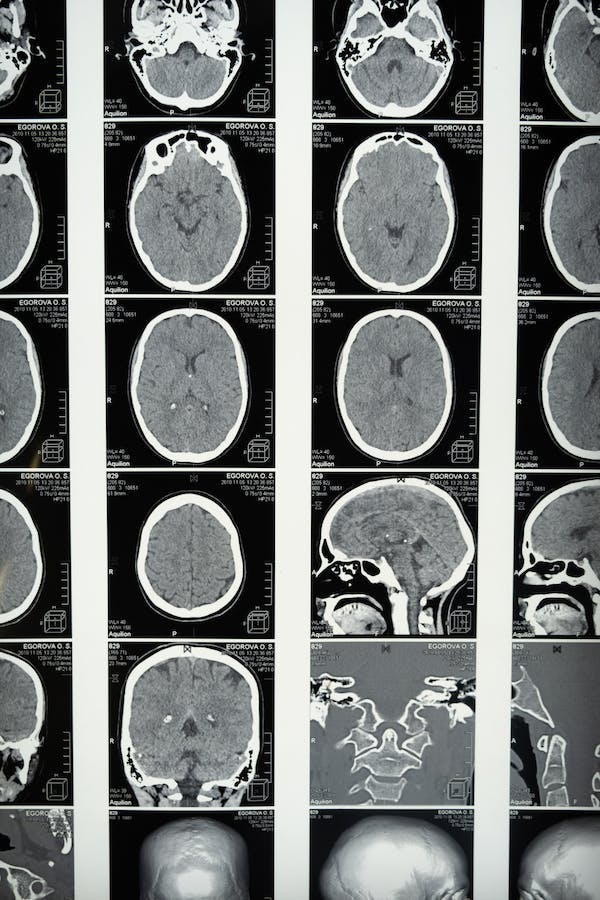

La afasia de Wernicke se produce, como no puede ser de otro modo, mediante la afectación del área de Wernicke. Esta zona se encuentra en la porción posterior del lóbulo temporal superior, en estrecha proximidad con el área auditiva primaria. Se extiende hacia la cisura de Silvio y está delimitada anteriormente por el área de Brodmann 22.

Específicamente, se subdivide en dos regiones conocidas como el área de asociación auditiva temporal superior y el área de asociación visual temporal inferior. Así, su principal función es la comprensión del lenguaje, ya sea a través de los estímulos auditivos o visuales que llegan a la persona.

Las causas de la afasia de Wernicke suelen estar asociadas con daños en el lóbulo temporal posterior y el lóbulo parietal superior, concretamente en la región perisilviana de la corteza cerebral. Estas lesiones pueden ser resultado de diversos factores, tales como (Zhang et al., 2006):